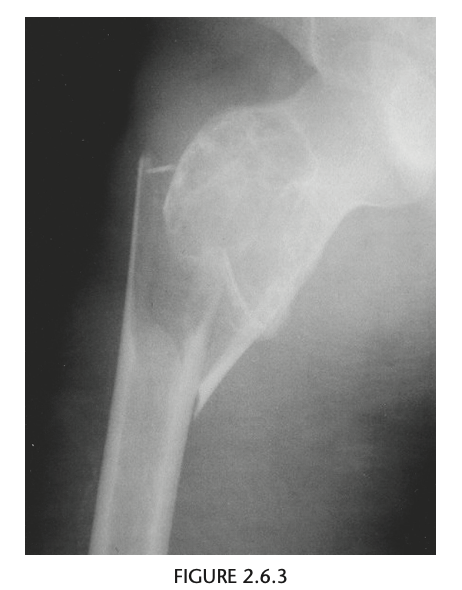

An anteroposterior view of the pelvis

shows flaring of the metaphyseal regions of

the proximal femurs and numerous osteochondromas

arising from the right iliac crest, pubic bones, and proximal right femur (arrows).

Axial CT through upper pelvis - Large right exostosis with soft tissue mass.

AP radiograph of knee - multiple osteochondromas arising from femur and fibula.

DIAGNOSIS: Multiple hereditary exostosis

AD disorder age 10-20s

Signs of malignant transformation - Growth of previous stable exostosis, new or increasing calcifications, new bony erosion

Associated with chondrosarcoma